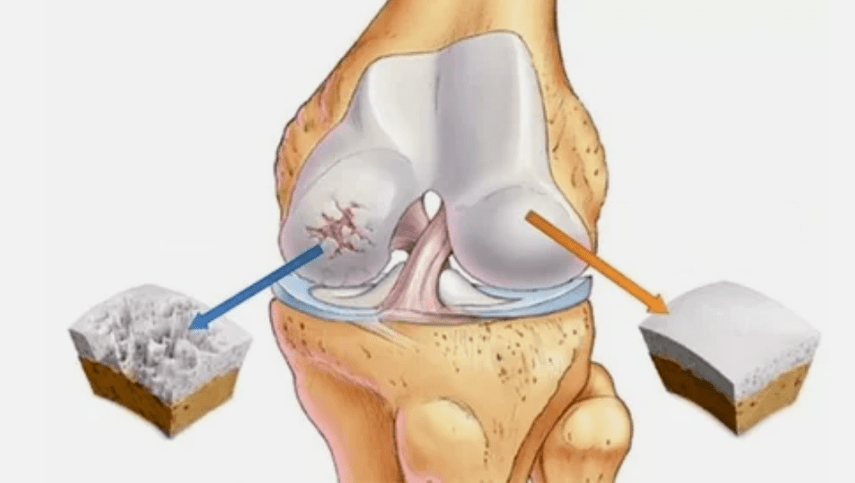

- The primary lesion affects Hijalin cartilage.In the case of circulatory disorders, there is a pathological deterioration of power.It is the first step or cause, which can reach arthrosis.

- Pathologies of hyaline coatings.The cartilage fabrics leads to replacement of pathological tissues - bone structures.

- Anomal growth appears on cartilage - osteophytes.

- Precedent violation of the natural anatomy of cartilage and bones causes overload of healthy cartilage areas.Destruction of articulated tissues without treatment is constantly progressing and leading to disability.

When the degree of disease increases, pathological processes are still worse.In the end, all Hijalin cartilage was destroyed.